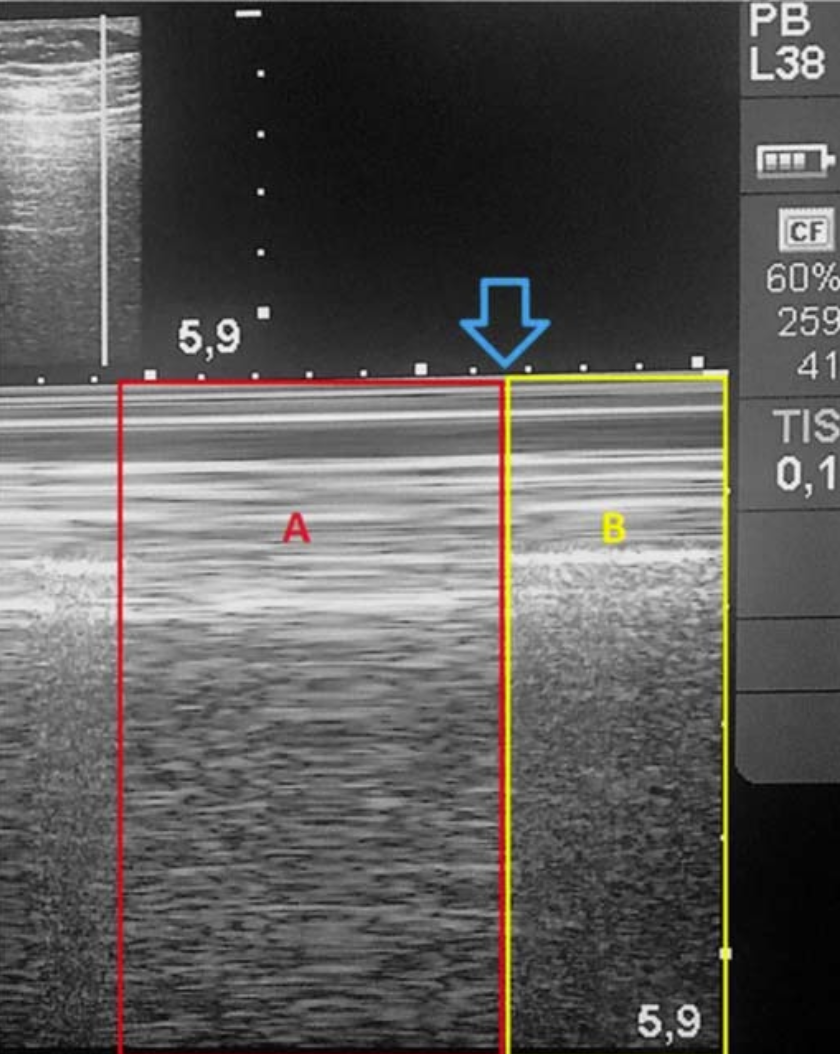

在 M 型超声上,正常的胸膜滑动征表现为「沙滩征」,气胸时则变为「条码征」(图 3),但以「肺点征」对气胸的特异性最大,可达 100%。所谓「肺点征」是指「沙滩征」与「条码征」相互过渡的区域(图4)。